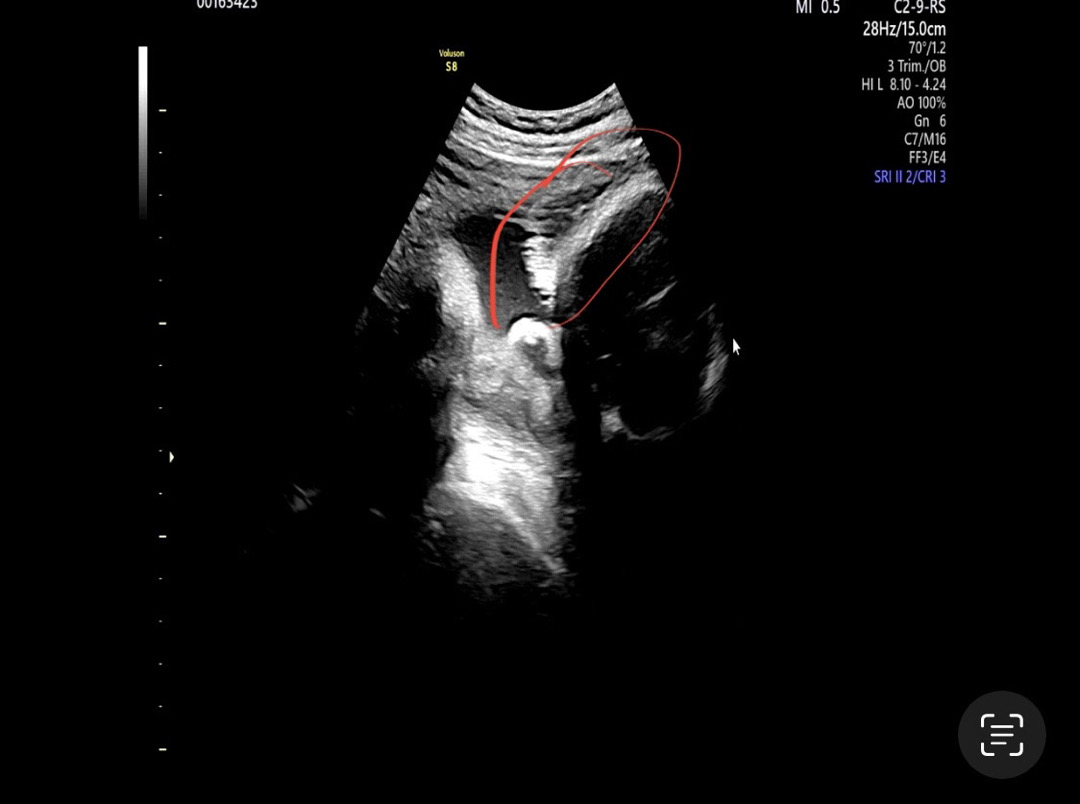

동그라미 친게 머리카락이 양수에 휘날리는거라는데 ㅎㅎ 31주에 저정도면 숱이 많은 아가려나요!

저희 아가 머리카락이요ㅋㅋ